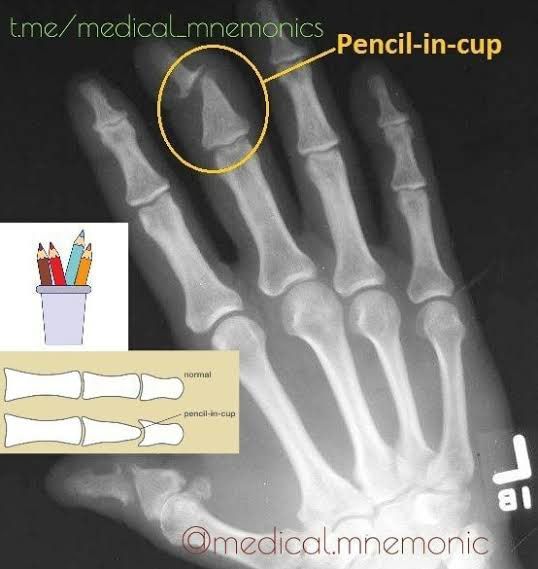

Pencil in cup deformity

“Pencil in cup” is a rare type of deformity in the distal interphalnageal joints of hands and feet seen in patients with Psoariatic Arthritis.